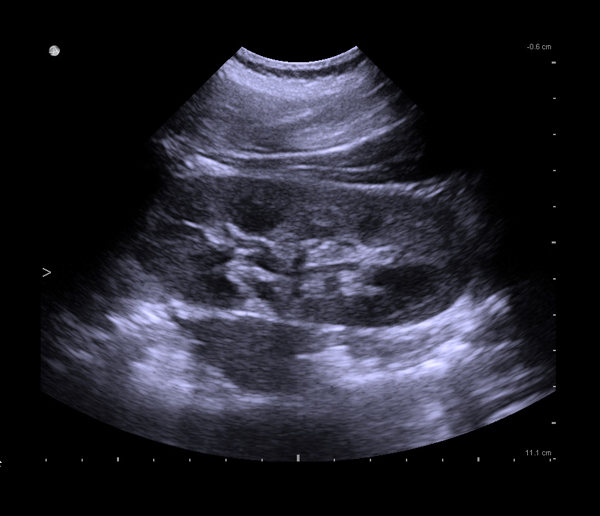

Ultrasound for Kidney

BK Medical systems provide high-resolution image quality for advanced kidney imaging, measurement, and biopsy. See anatomical details and variations and find kidney stones. Visualize and measure blood flow with highly sensitive color Doppler.